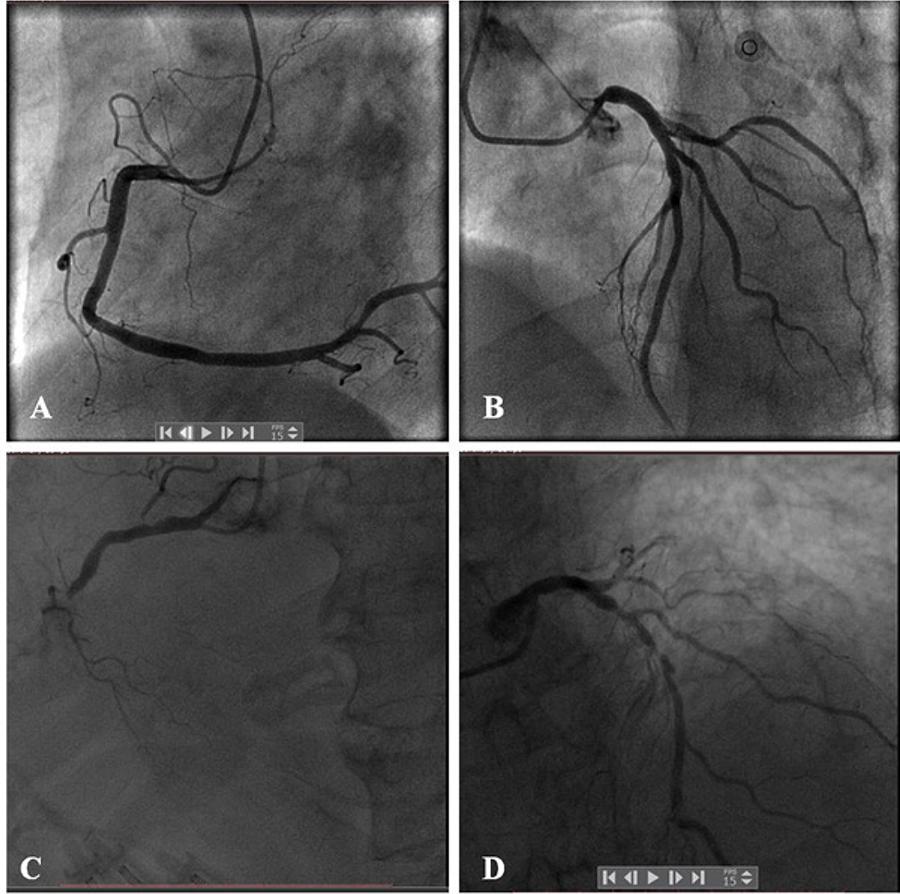

Foram incluídos pacientes submetidos à angiografia coronária (AGC), entre 2010 e 2017, com câncer de pulmão prévio. Os fatores de risco associados à DAC e os dados sobre o câncer de pulmão foram avaliados. Avaliamos as anomalias das artérias coronárias de acordo com o escore SYNTAX (SXescore) calculado à AGC. Na análise de regressão logística, o escore SYNTAX foi classificado como alto (SXescoreALTO) se ≥22. Os dados foram analisados através de estatística descritiva e análise de regressão.

Ao todo, 94 pacientes foram incluídos no estudo. O SXescore foi mais alto no grupo com quimioterapia quando comparado com o grupo sem quimioterapia (25,25, IIQ [4,50–30,00] versus 16,50, IIQ [5,00–22,00]; p = 0,0195). A taxa do SXescoreALTO foi maior no grupo com quimioterapia do que no no grupo sem quimioterapia (58,33% versus 25,86; p = 0,0016). Tanto a análise de regressão logística univariada (OR: 4,013; 95% IC:1,655–9,731) quanto a multivariada (OR: 5,868; 95% IC:1,778–19,367) revelaram que a quimioterapia aumentou o risco de uma maior taxa do SXescoreALTO. A análise multivariada de regressão logística Stepwise mostrou que o risco para DAC anatômica mais grave aumenta com a quimioterapia como um todo em 5.323 vezes (95% IC: 2,002–14,152), e com o regime à base de platina em 5,850 vezes (95% IC: 2,027–16,879).